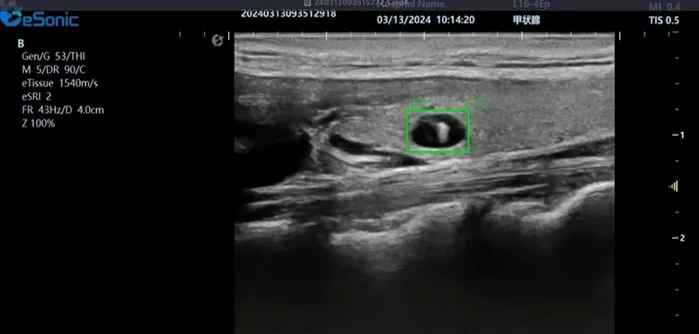

hjc888黄金城官网医疗(ESI)表示,其最新的人工智能功能可以帮助到医疗机构的工作效率,功能包括,实时、动态、快速自动识别病灶,良恶性病灶概率预测,甲状腺结节和乳腺的二维灰阶动态自动实时检测需求,提供多个结节动态检测轮廓框。实时获取多幅具备临床特征(大小、属性等)的结节切面,同时提供当前切面所示结节的结节大小、属性特征、TI-RADS 分级。

对于甲状腺结节相关的自动检测功能,甲状腺结节病灶检出率≥95%,良恶性分类灵敏度≥90%、良恶性分类特异度≥85%。